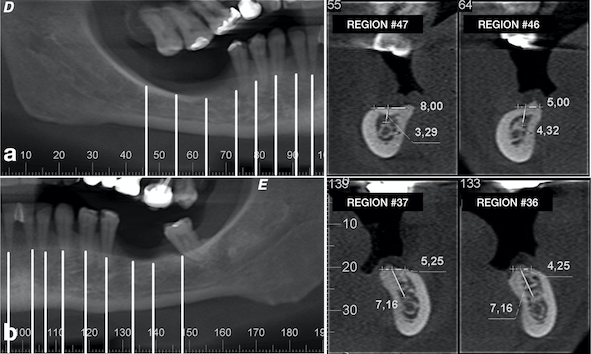

A 49-year-old patient attended a private dental office in the city of Fortaleza, CE, Brazil, for rehabilitation of an atrophic posterior mandible. During anamnesis, no systemic disease was reported. Clinical evaluation showed absence of teeth #36, #37, #46, #47 and #48 and significant bone resorption in these regions (Fig. 1a), including extrusion of teeth #16, #17 and #18 (Fig. 1b). Cone-beam computed tomography (CBCT) showed that the patient had a limited bone height in the region of teeth #46 and #47 with a distance of 3-4 mm between the bone crest and mandibular canal thus hindering the placement of implants (Fig. 2a). With regard to the left lower region, there was enough bone for the placement of 6-mm implants in the region of teeth #36 and #37, as well as the presence of Grade-III furcation defect and alveolar bone loss in the region of tooth #38 (Fig. 2b). The case report was approved by the Research Ethics Committee of the University of Santo Amaro. Before the treatment, the informed consent form was presented and signed by the patient.

After one month from the surgical procedure, a T-plate was placed (Neodent®, Curitiba, PR, Brazil) in the buccal region and also a mini-implant (Neodent®, Curitiba, PR, Brazil) in the palatal region between teeth #17 and #18 (Fig. 6a). Moreover, two brackets (Morelli, Sorocaba, SP, Brazil) were also bonded to these teeth for activation of the plate and mini-implant in order to intrude them, thus creating space for placement of the prostheses (Fig. 6b). After six months, another CBCT was performed to assess the vertical and horizontal reconstruction. There was vertical bone augmentation in the region of teeth #46 and #47, respectively, by 2.68 mm and 3.21 mm (Fig. 7), which allowed the placement of 6-mm implants. The same medication and anaesthetic protocol used in previous surgery were used for this surgical step. A mucoperiosteal incision in the alveolar crest was performed (Fig. 8a), followed by a detachment of the flap and placement of two implants of 4.1 x 6.0 mm (Standard Plus SLActive, Roxolid®, Straumann, Basel, Switzerland) according to the manufacturer’s instructions (Fig. 8b) and (Fig. 8 and c). Post-operative medication and guidance were the same used after placement of implants on the contralateral side.